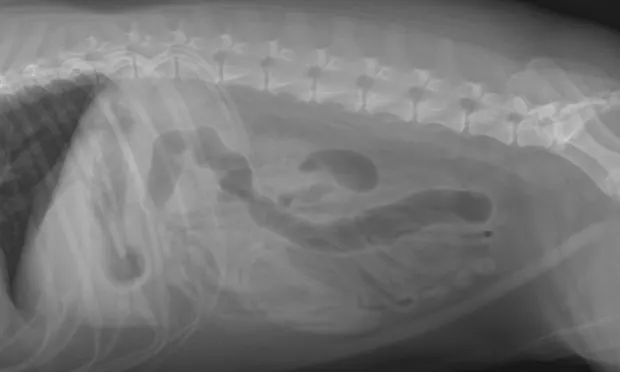

Remember to develop the films with fresh, clean developing solutions-old or exhausted developer will not work for developing technique charts. Examine the films for the setting that gives the best diagnostic quality. In Figure A, the kVp was 56, mA setting was 200, and time was 0.0125 seconds (mAs = 2.5). In this example, the bones are not easily visualized and the film overall is too white (underexposed).

In Figure B, the kVp and mA were left the same and the time was changed to 0.025 seconds (mAs = 5). In this image, the body wall, abdominal organs, and bones can all be readily visualized; this is a proper exposure. In Figure C, the kVp and mA were left the same and the time was changed to 0.05 seconds (mAs = 10). With this higher exposure technique, the ventral body wall cannot be visualized, and the abdomen is too dark (overexposed).